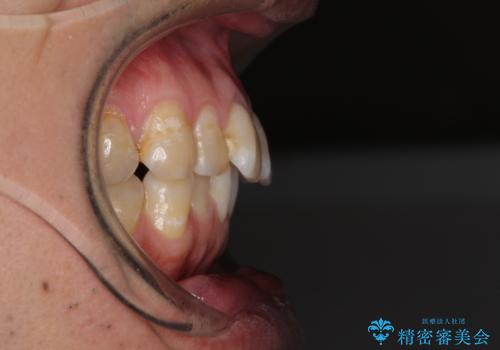

前歯のデコボコと下顎の八重歯 インビザラインによる矯正治療

- 前歯のデコボコや八重歯を気にして来院された患者様です。

インビザラインを用いて、歯列を整えることとしました。